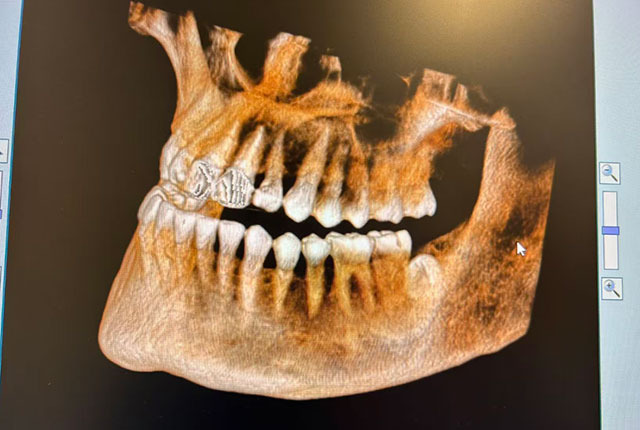

据了解,送来锦旗的龙女士在贵阳上班,长期被智齿折磨,在当地医院检查后,发现智齿完全呈现水平阻生状态,拔除难度较大。加上龙女士本身怕疼,一直忍着没有拔掉,便回到泸州,找到了彭培钊医生。

但要说人体最不按套路生长的零件,智齿一定榜上有名,它可以斜着长、横着长、倒着长……乱长,各有各的花样。

2.方位不正的智齿。如果智齿长出的空间不足,不易清洁,容易引起智齿冠周炎。有的智齿向前倾倒,与前一颗磨牙食物嵌塞还会导致前一颗磨牙蛀坏。

4.没完全长出的智齿。智齿部分埋在齿槽骨里,牙龈形成盲袋,经常发炎,甚至引起面部肿胀,必须拔掉。